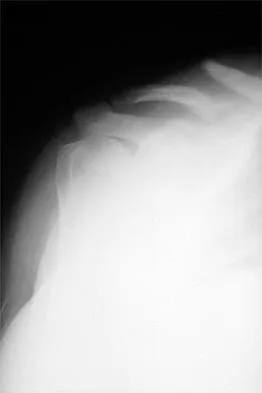

A 72-year-old woman who was doing well after undergoing total shoulder arthroplasty for arthritis 4 months ago is suddenly unable to elevate her arm. Examination reveals 70 degrees of external rotation compared with 45 degrees on the uninvolved side, and she is unable to lift her hand off her lower back. Radiographs are shown in Figures 43a through 43c. Treatment should consist of

Explanation